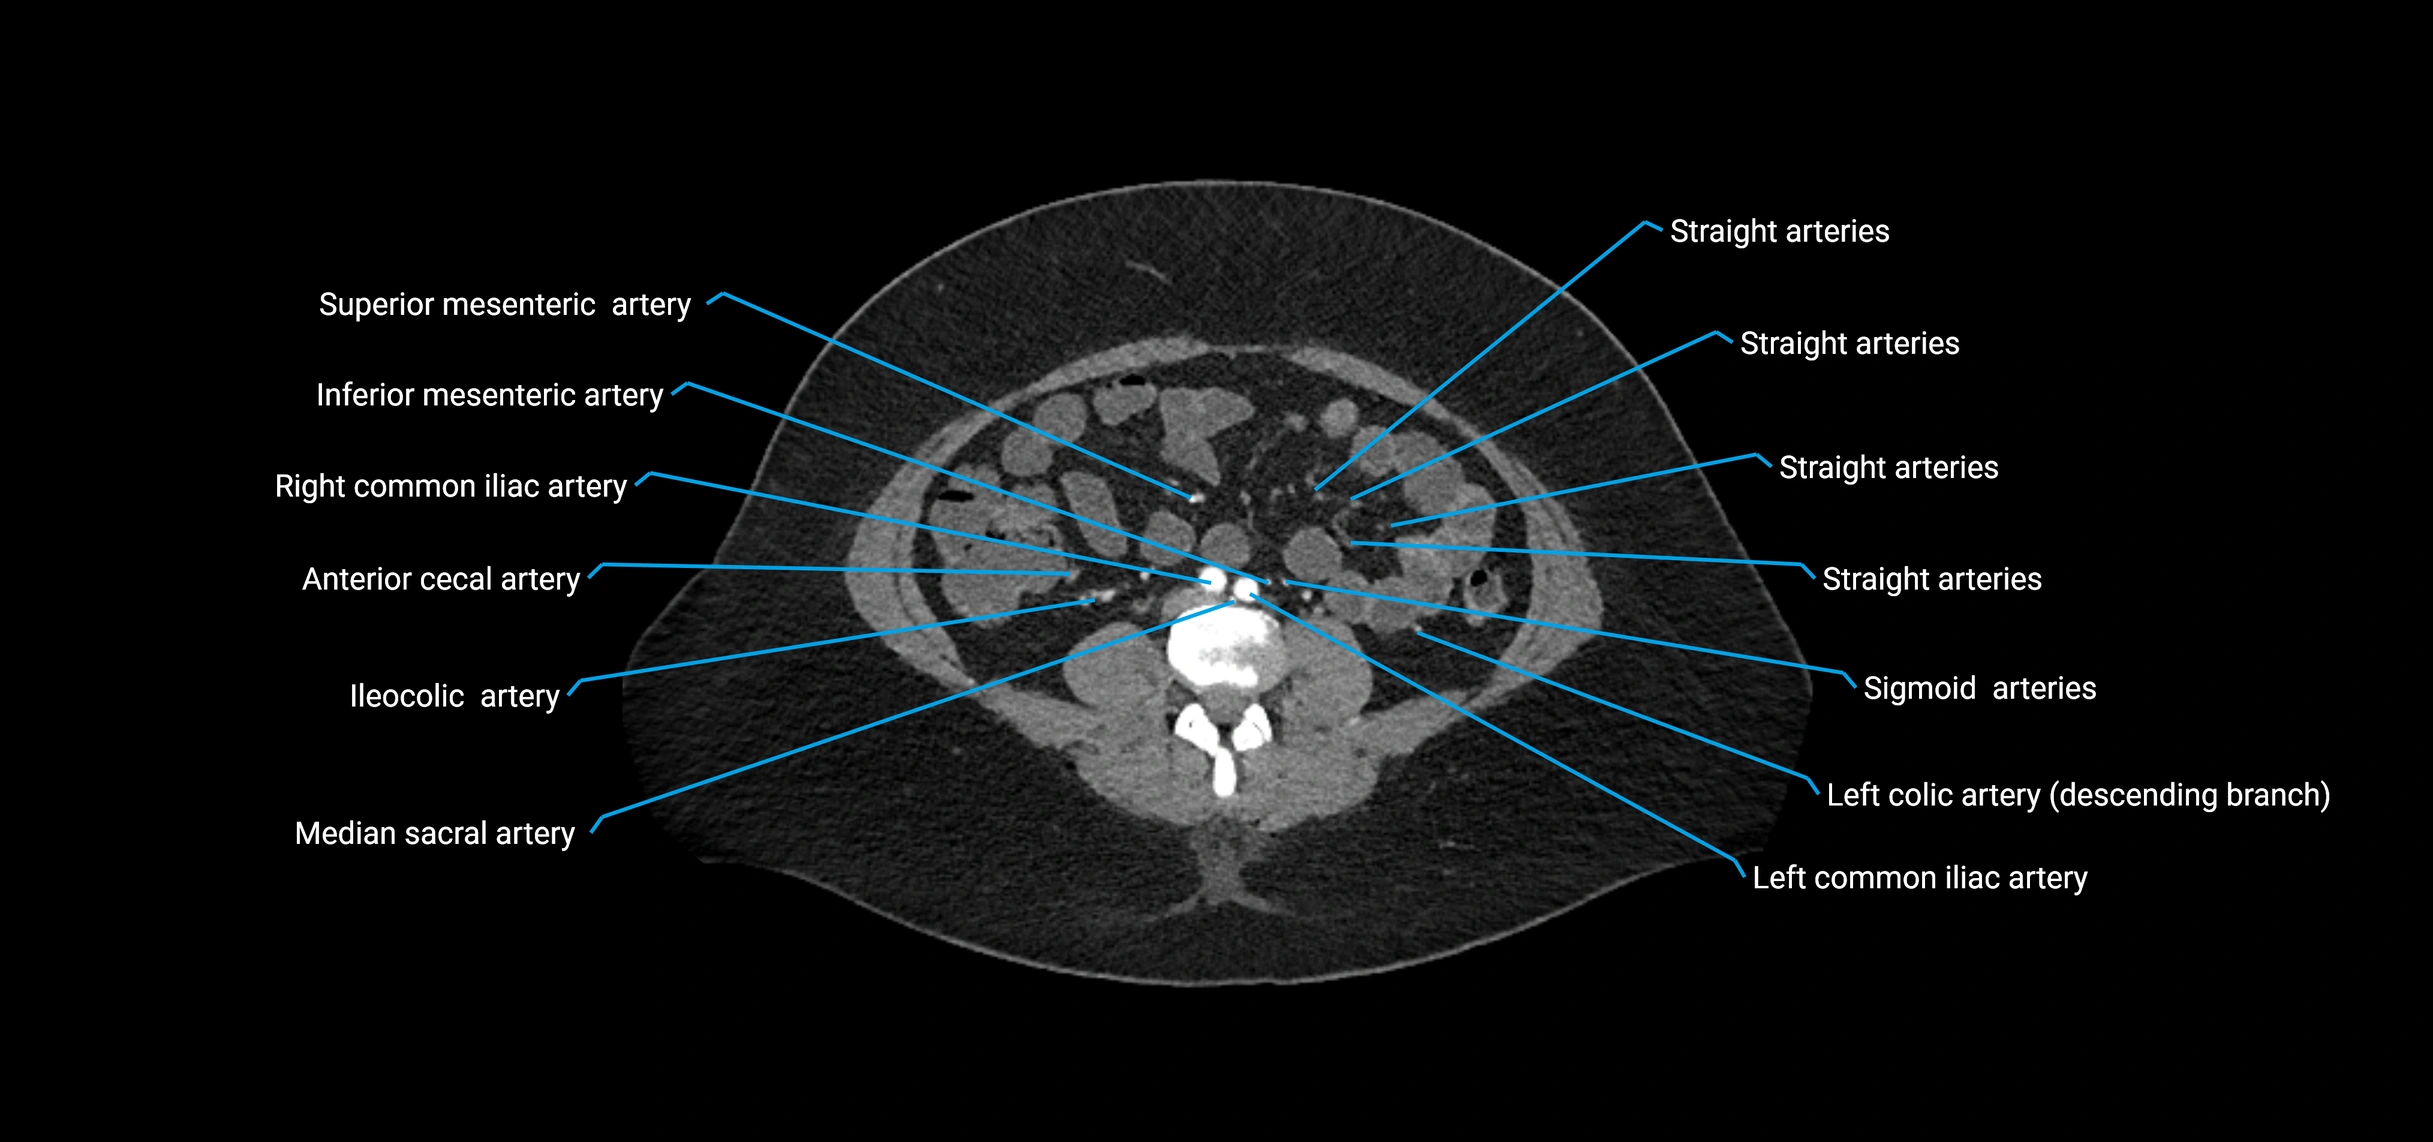

Contrast-enhanced CT (CTA):

• Gold standard for abdominal aortic imaging

• Provides excellent detail of lumen, wall, aneurysm, thrombus, and branch vessels

• Multiplanar and 3D reconstructions help in aneurysm measurement, stent graft planning, and dissection evaluation

• Detects acute rupture, traumatic injury, or occlusion with high sensitivity